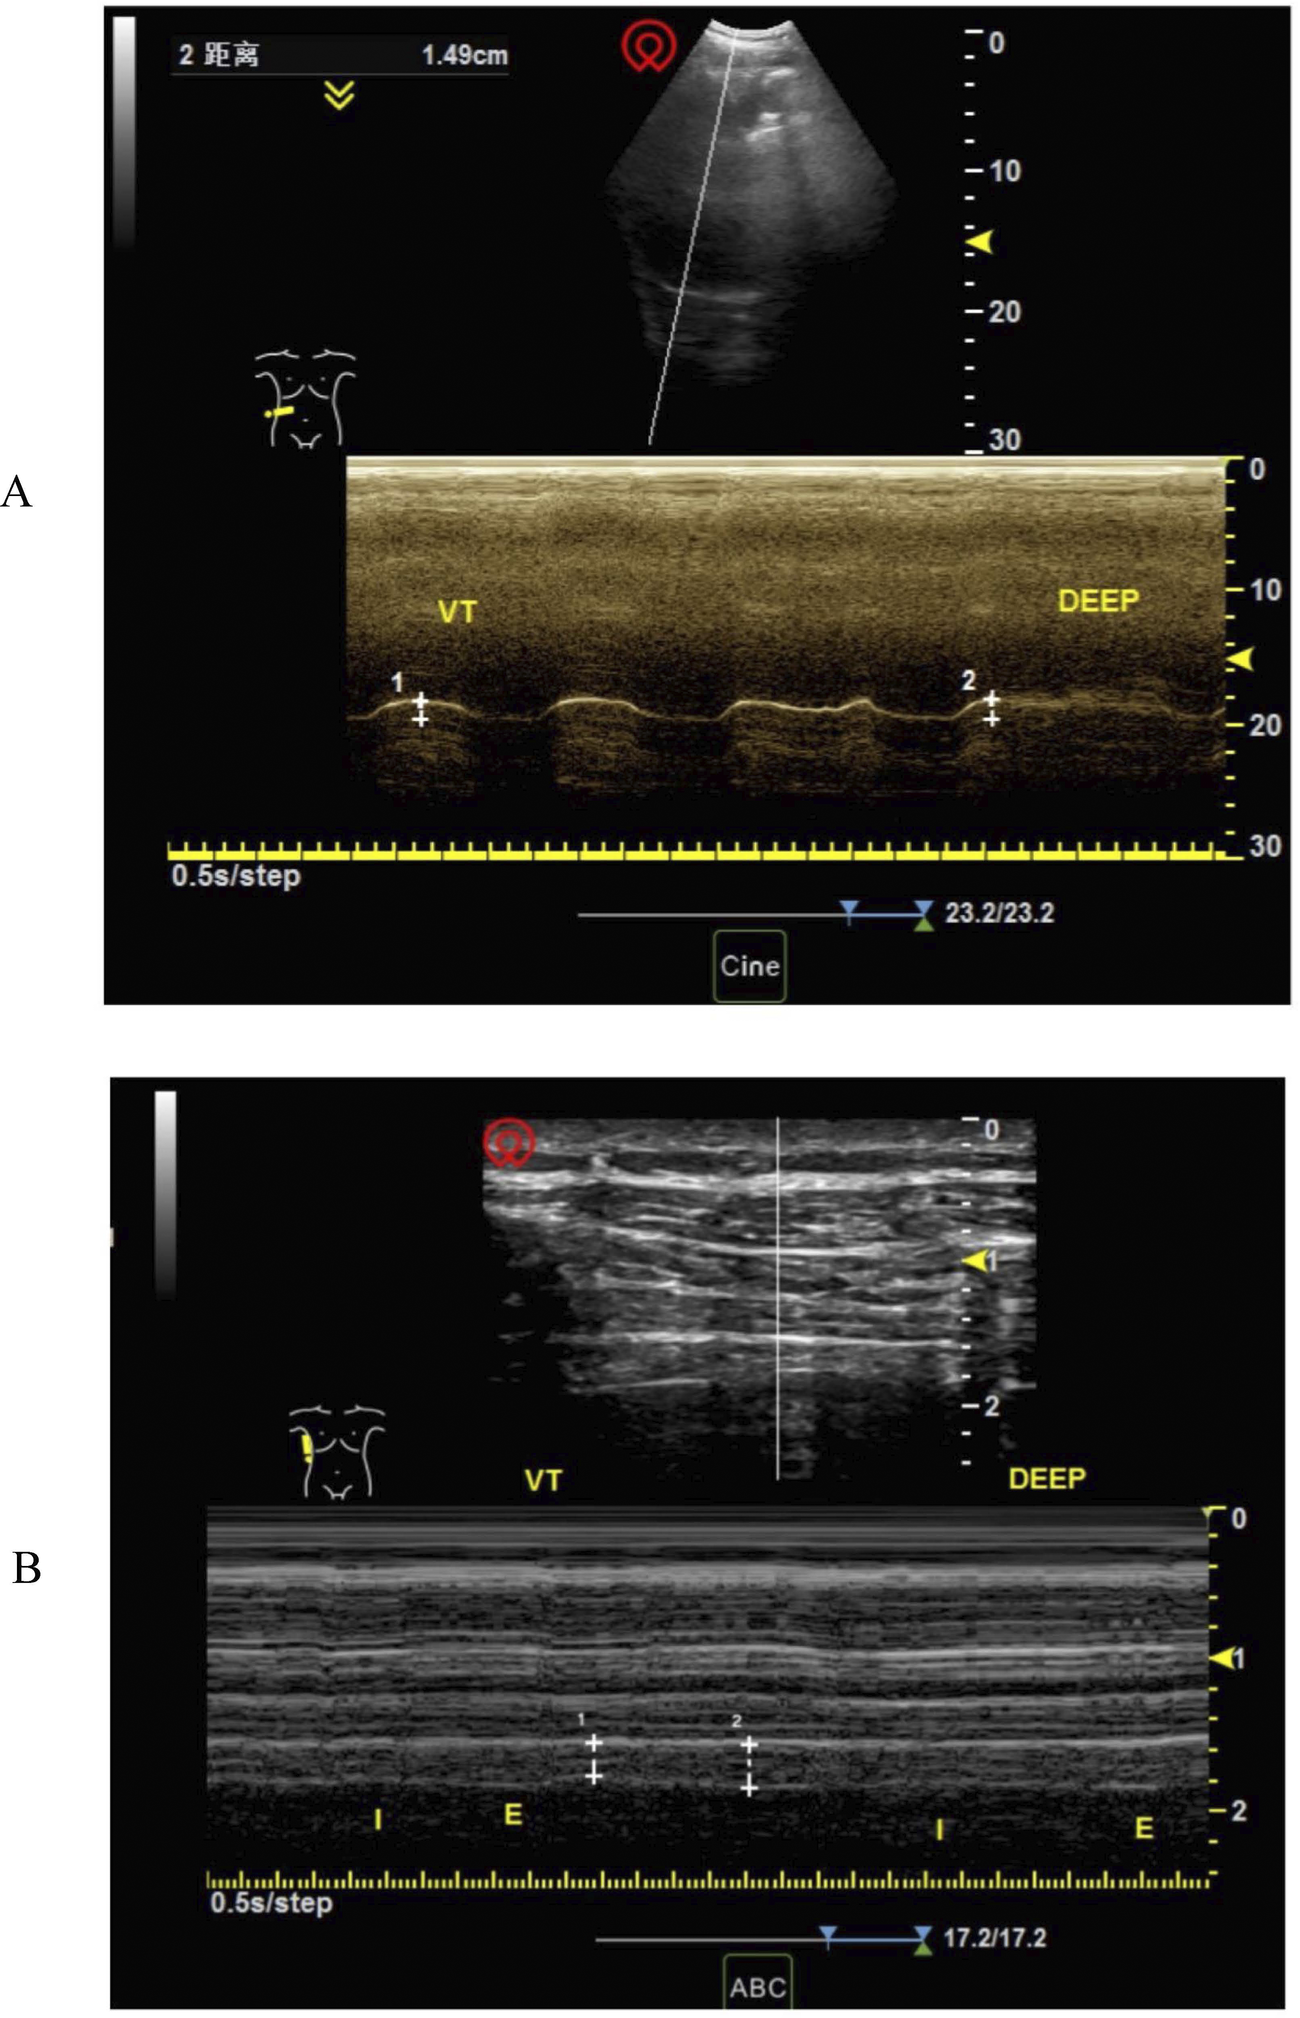

The diaphragmatic pictures of the screened patients met the following criteria: bilateral diaphragmatic activity and bilateral diaphragmatic thickness could be clearly measured, and three continuous respiratory cycles could be shown in a single picture. Diaphragmatic activity was measured during breathing at rest because postoperative pain, sternotomy, and other factors might affect the patient's effort during forced breathing or sniffing (12). The details of the measurements were as follows. To measure diaphragmatic activity, the probe was positioned at the inferior margin of the costal arch to observe diaphragmatic activity through the acoustic window of the liver or spleen. The distance between the end of inspiration and expiration was taken in the M mode as the diaphragmatic excursion (Figure 1). The average diaphragmatic activity was then calculated over three consecutive respiratory cycles. To determine the fraction of diaphragmatic thickness, the probe was placed perpendicularly to the chest wall at the mid-axillary line (T6-8) until the three-layer structure (pleura-diaphragm-peritoneum) could be observed under the B mode. The diaphragmatic thickness at the end of inspiration and expiration was calculated in M mode (Figure 1). The diaphragmatic thickness fraction was calculated as (end-inspiratory thickness to end-expiratory thickness)/end-expiratory thickness × 100%, and the average value of three consecutive respiratory cycles was calculated. On the basis of previous literature, diaphragmatic dysfunction in this study was defined as resting diaphragmatic excursion of less than 9 mm for women and less than 10 mm for men (8, 19, 20), and the average diaphragm thickness fraction was less than 20% (5, 9). Consequently, the participants were categorized into a normal diaphragm function group (Normal group) and a diaphragm dysfunction group (DD group).

Figure 1

Measurement of right diaphragm excursion and thickness at rest. (A) Measurement of right diaphragm excursion at rest (B) measurement of diaphragm thickness at rest.